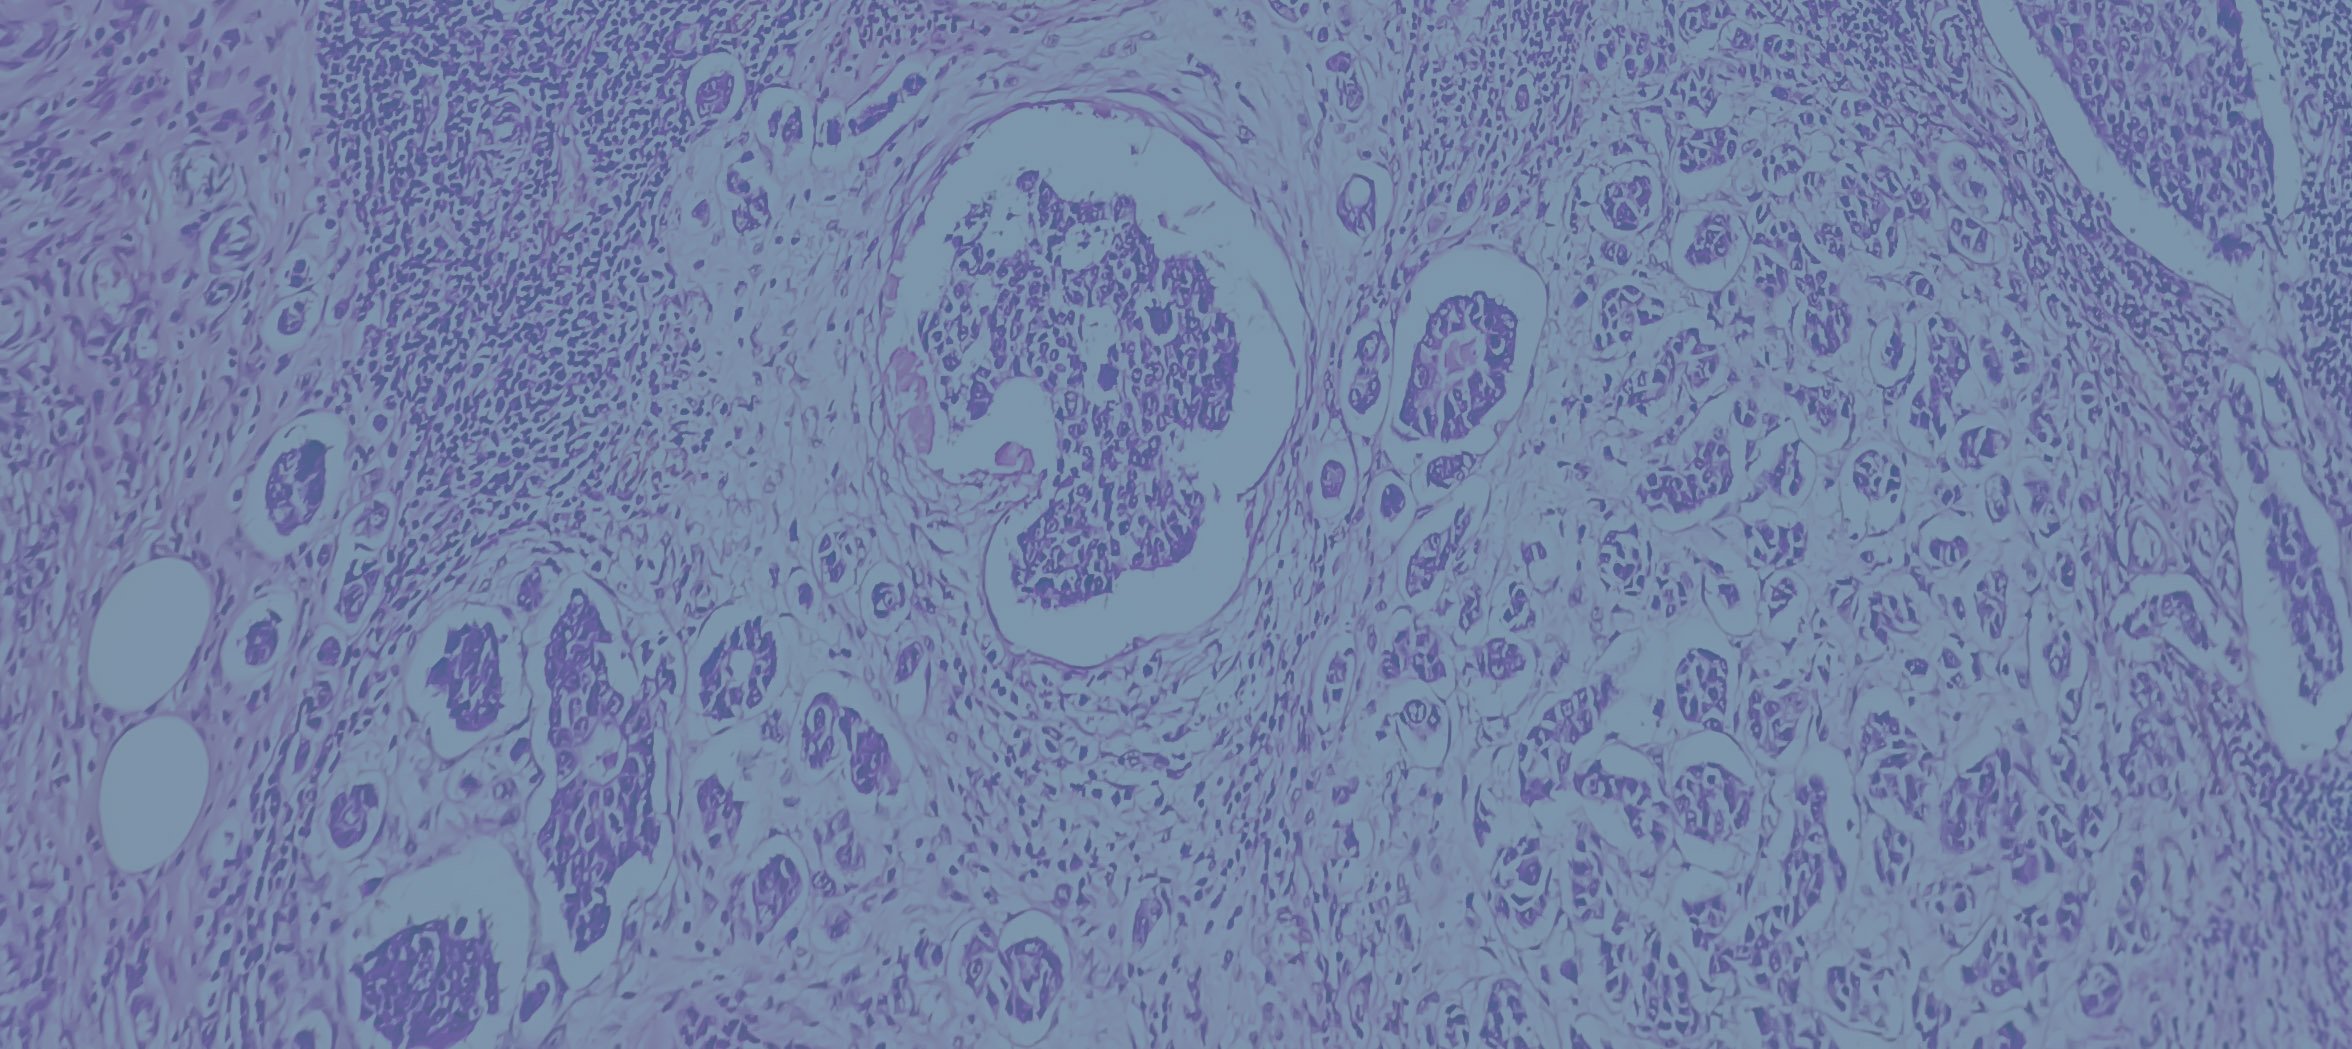

Breast cancer occurs when cells within the breast begin to grow abnormally and uncontrollably, forming a lump or mass. These cells can sometimes spread beyond the breast to nearby lymph nodes or other parts of the body. There are several different types of breast cancer, and treatment is always tailored to the individual.

• Ductal carcinoma in situ (DCIS) – an early, non-invasive form of breast cancer confined to the milk ducts.

• Invasive ductal carcinoma (IDC) – the most common form of invasive breast cancer, arising from the milk ducts.

• Invasive lobular carcinoma (ILC) – arises from the lobules that produce milk and often presents more subtly on imaging.

Other, less common subtypes include inflammatory breast cancer and triple-negative breast cancer. Each type has unique features that influence treatment decisions, which I will discuss in detail during your consultation.